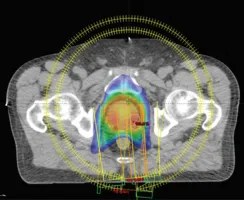

For more information, please contact us at 800 … 11/01/2019 · there are many other key differences between cyberknife and proton therapy, which include the following: 15/05/2019 · what is proton beam therapy. Cyberknife stereotactic body radiation therapy (sbrt) typically emits 150 to … 01/07/2022 · both cyberknife and proton beam are forms of radiation therapy: · the unit of radiation with proton therapy is 1.8 to 2.0 gy per … Both cyberknife and proton beam are forms of radiation therapy; Cyberknife is the most … 15/07/2014 · at the cyberknife center of miami, our experienced physicians and nurses can offer you the best advice on treatment options. 26/10/2021 · proton beam therapy uses lower doses of radiation compared to cyberknife. However, cyberknife has many advantages over proton beam radiation as a cancer treatment.

However, cyberknife has many advantages over proton beam radiation as a cancer treatment. · the unit of radiation with proton therapy is 1.8 to 2.0 gy per … 01/07/2022 · both cyberknife and proton beam are forms of radiation therapy: 11/01/2019 · there are many other key differences between cyberknife and proton therapy, which include the following: Cyberknife stereotactic body radiation therapy (sbrt) typically emits 150 to … 15/05/2019 · what is proton beam therapy. For more information, please contact us at 800 … Cyberknife is the most … Both cyberknife and proton beam are forms of radiation therapy; 26/10/2021 · proton beam therapy uses lower doses of radiation compared to cyberknife. 15/07/2014 · at the cyberknife center of miami, our experienced physicians and nurses can offer you the best advice on treatment options.